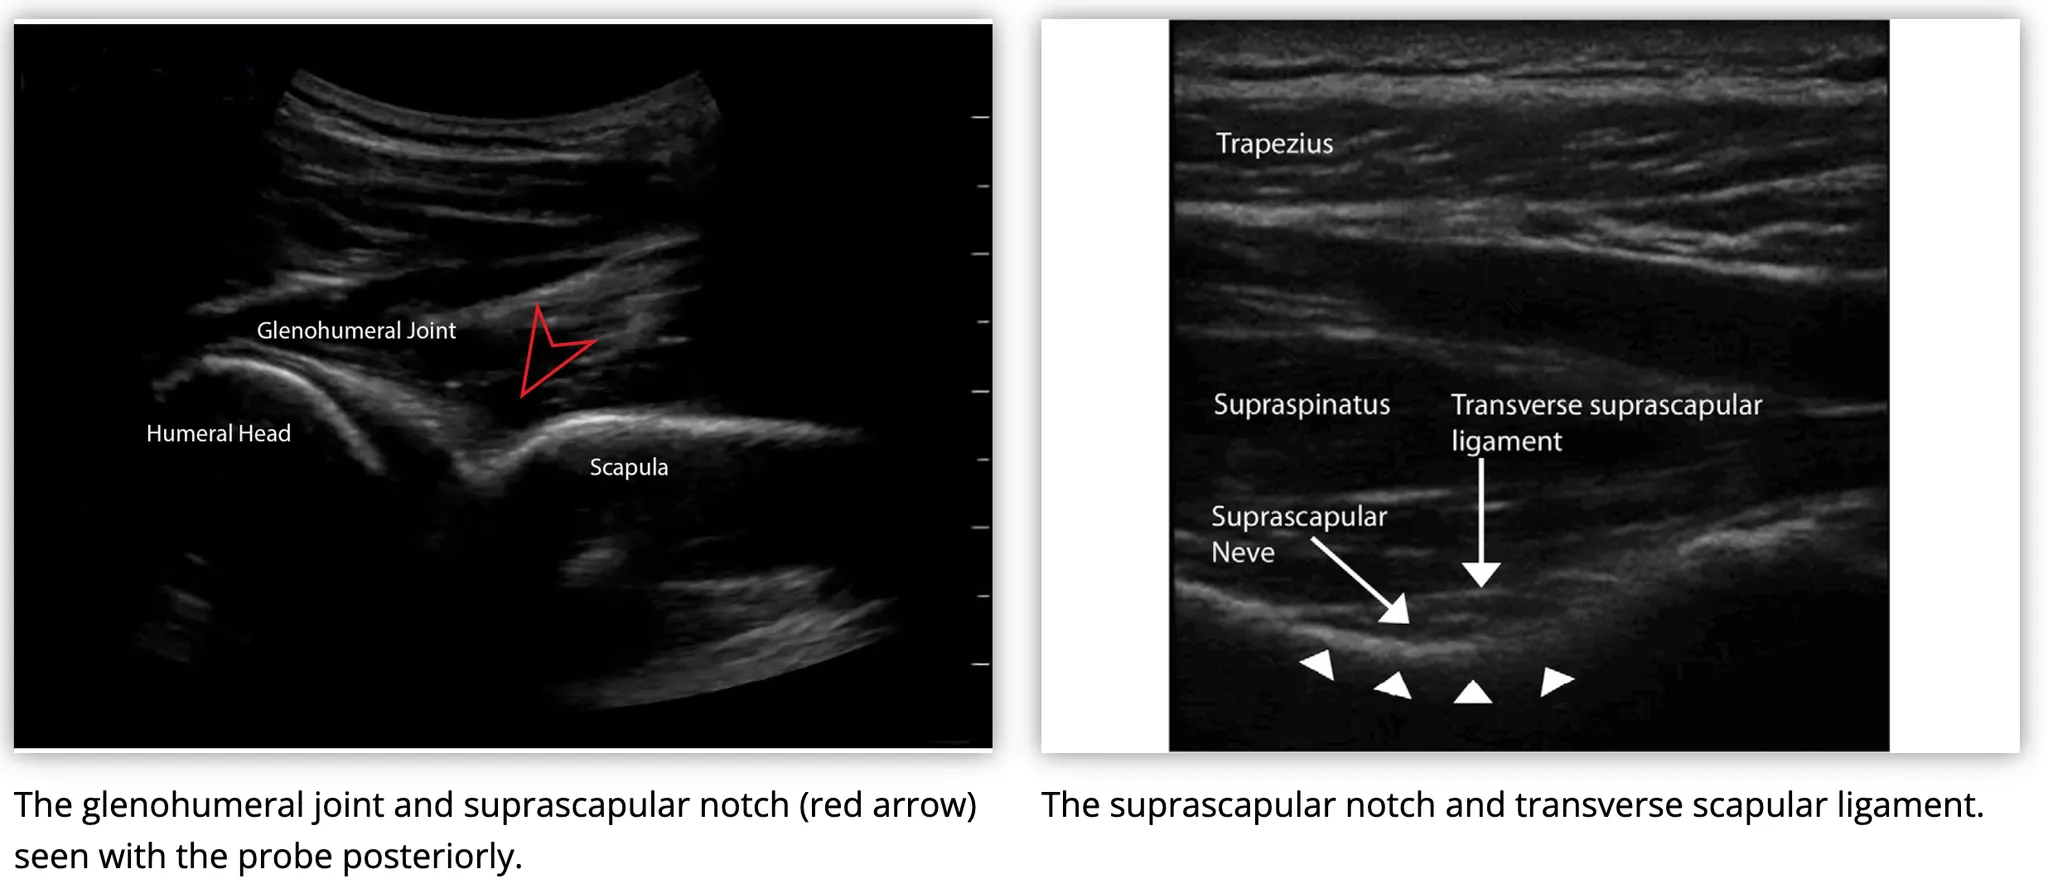

Suprascapular nerve

Sensory innervation : acromioclavicular joint, glenohumeral joint

SSNB : US-guided, Prilocaine 20ml/400mg injected